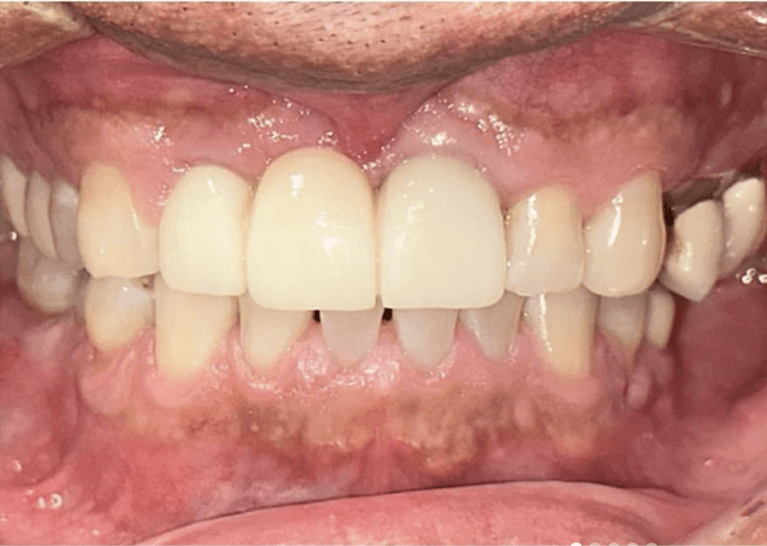

Failed front teeth bridge, replaced with implant bridge.